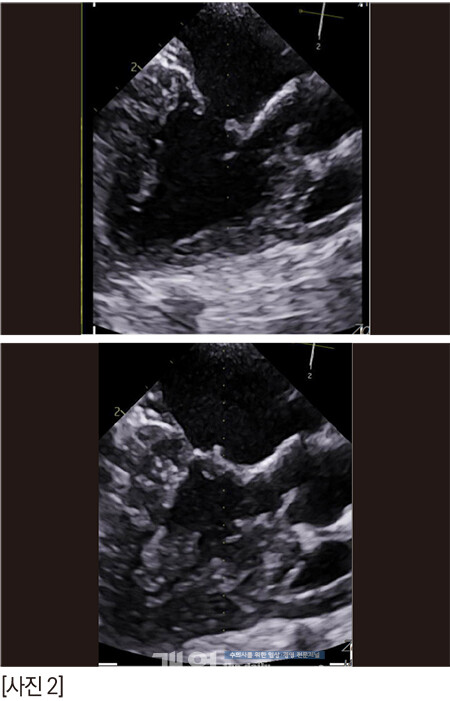

경흉부 심장초음파에서의 소견은 다음과 같다.

- 이첨판; 경미한 퇴행성 변화/ slight MVP

- LVIDDn; 1.24 1.5 1.99

- LA/AO; 1.67 1.29 1.74

- RF(Regurgitant Fraction); 37% / RV(Regurgitant volume); 0.98ml/kg

- AR; 4.0m/s

1. ACVIM MMVD stage B1->B2 w/ slight MVP

- 이전 대비 LA, LV volume overload 진행

- LAP 지표 상승: 폐수종 및 임상증상 발전 가능성에 대한 주의 필요

- MVP; chordae tendinae elongation 가능성, MV 정밀평가 위한 TEE 고려

2. TVI w/ high probability of PH

3. AR (mild or mild to moderate)

이첨판 역류량이 severe는 아니지만, 진행성이기 때문에 긴장을 좀 해야겠다.

그래서 TEE 를봤다.

zone 2의 스틸컷이다. 어때 보이는가? 잘 닫히고 괜찮은가?

anterior leaflet의 끝단이 flail 되고 있다. 늘상 만나는 심각한 수준의 아이들 보다는 좀 낫긴 한데, 퇴행성 변화로 판막의 끝단이 너덜거리고, anterior leaflet의 건삭은 조금씩 닳아서 끊어지고 있나보다. 끝단이 좌심방을 향해 있다.

anterior의 zone 2-3과 posterior의 zone 2가 좀 뒤집어지고 있다. 이것은 건삭의 일부가 끊어져 너덜거리는 것으로 예측한다. 2D에서는 역류가 심해 보이지 않았지만 3D에서는 꽤 심해 보인다.